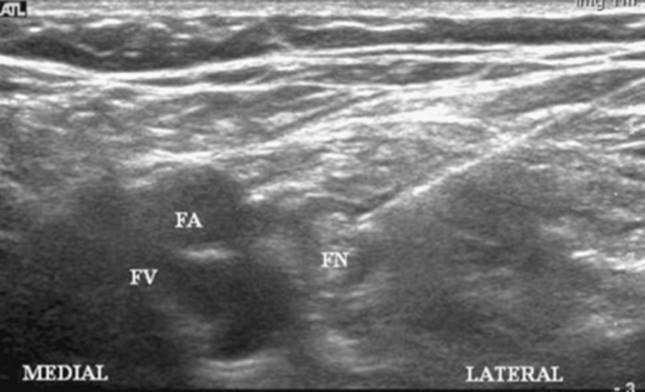

Ultrasound Landmarks: The femoral artery and the femoral nerve. The nerve lies lateral or occasionally deep to the artery (Fig. 39-1).

Figure 39-3. Femoral artery and hyperechoic nerve.